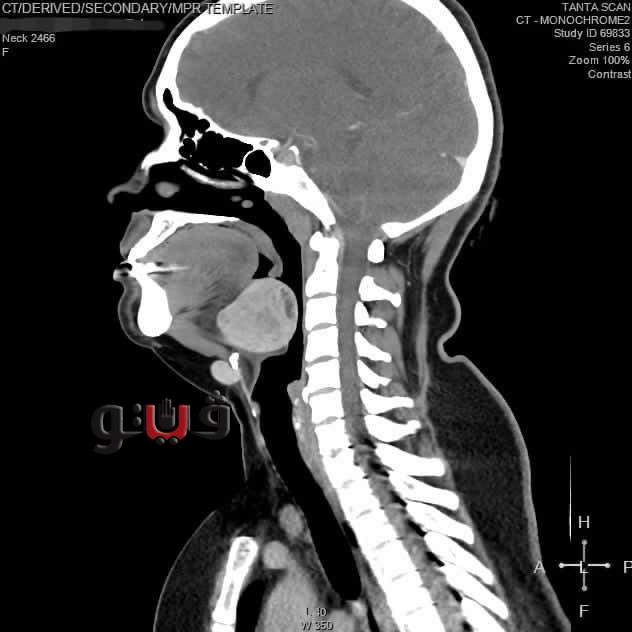

وأوضح الدكتور أحمد غنيم، عميد كلية الطب ورئيس مجلس إدارة المستشفيات الجامعية بطنطا، أن المريضة كانت تعاني من عيب خلقي نادر وهو وجود الغدة الدرقية بالجزء الخلفي من اللسان مما كان يسبب لها صعوبة في التنفس والبلع والاختناق أثناء النوم.

وأضاف عميد طب طنطا، أن تخدير المريضة كان يمثل تحدياً نظرًا لوجود الغدة الذي يماثل حجم البرتقالة في مجرى التنفس، لكن نجح فريق التخدير بتركيب أنبوب تنفس للمريضة بمنظار القصبة الهوائية بمهارة فائقة دون أن تشعر المريضة بأي ألم، بعدها قام الفريق الجراحي باستئصال الغدة من الفم باستخدام المنظار الجراحي.